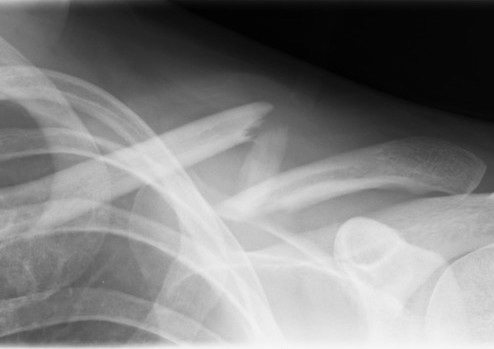

Compound clavicle fracture

Shorted / displaced midshaft clavicle fractures

Z shaped midshaft clavicle fracture